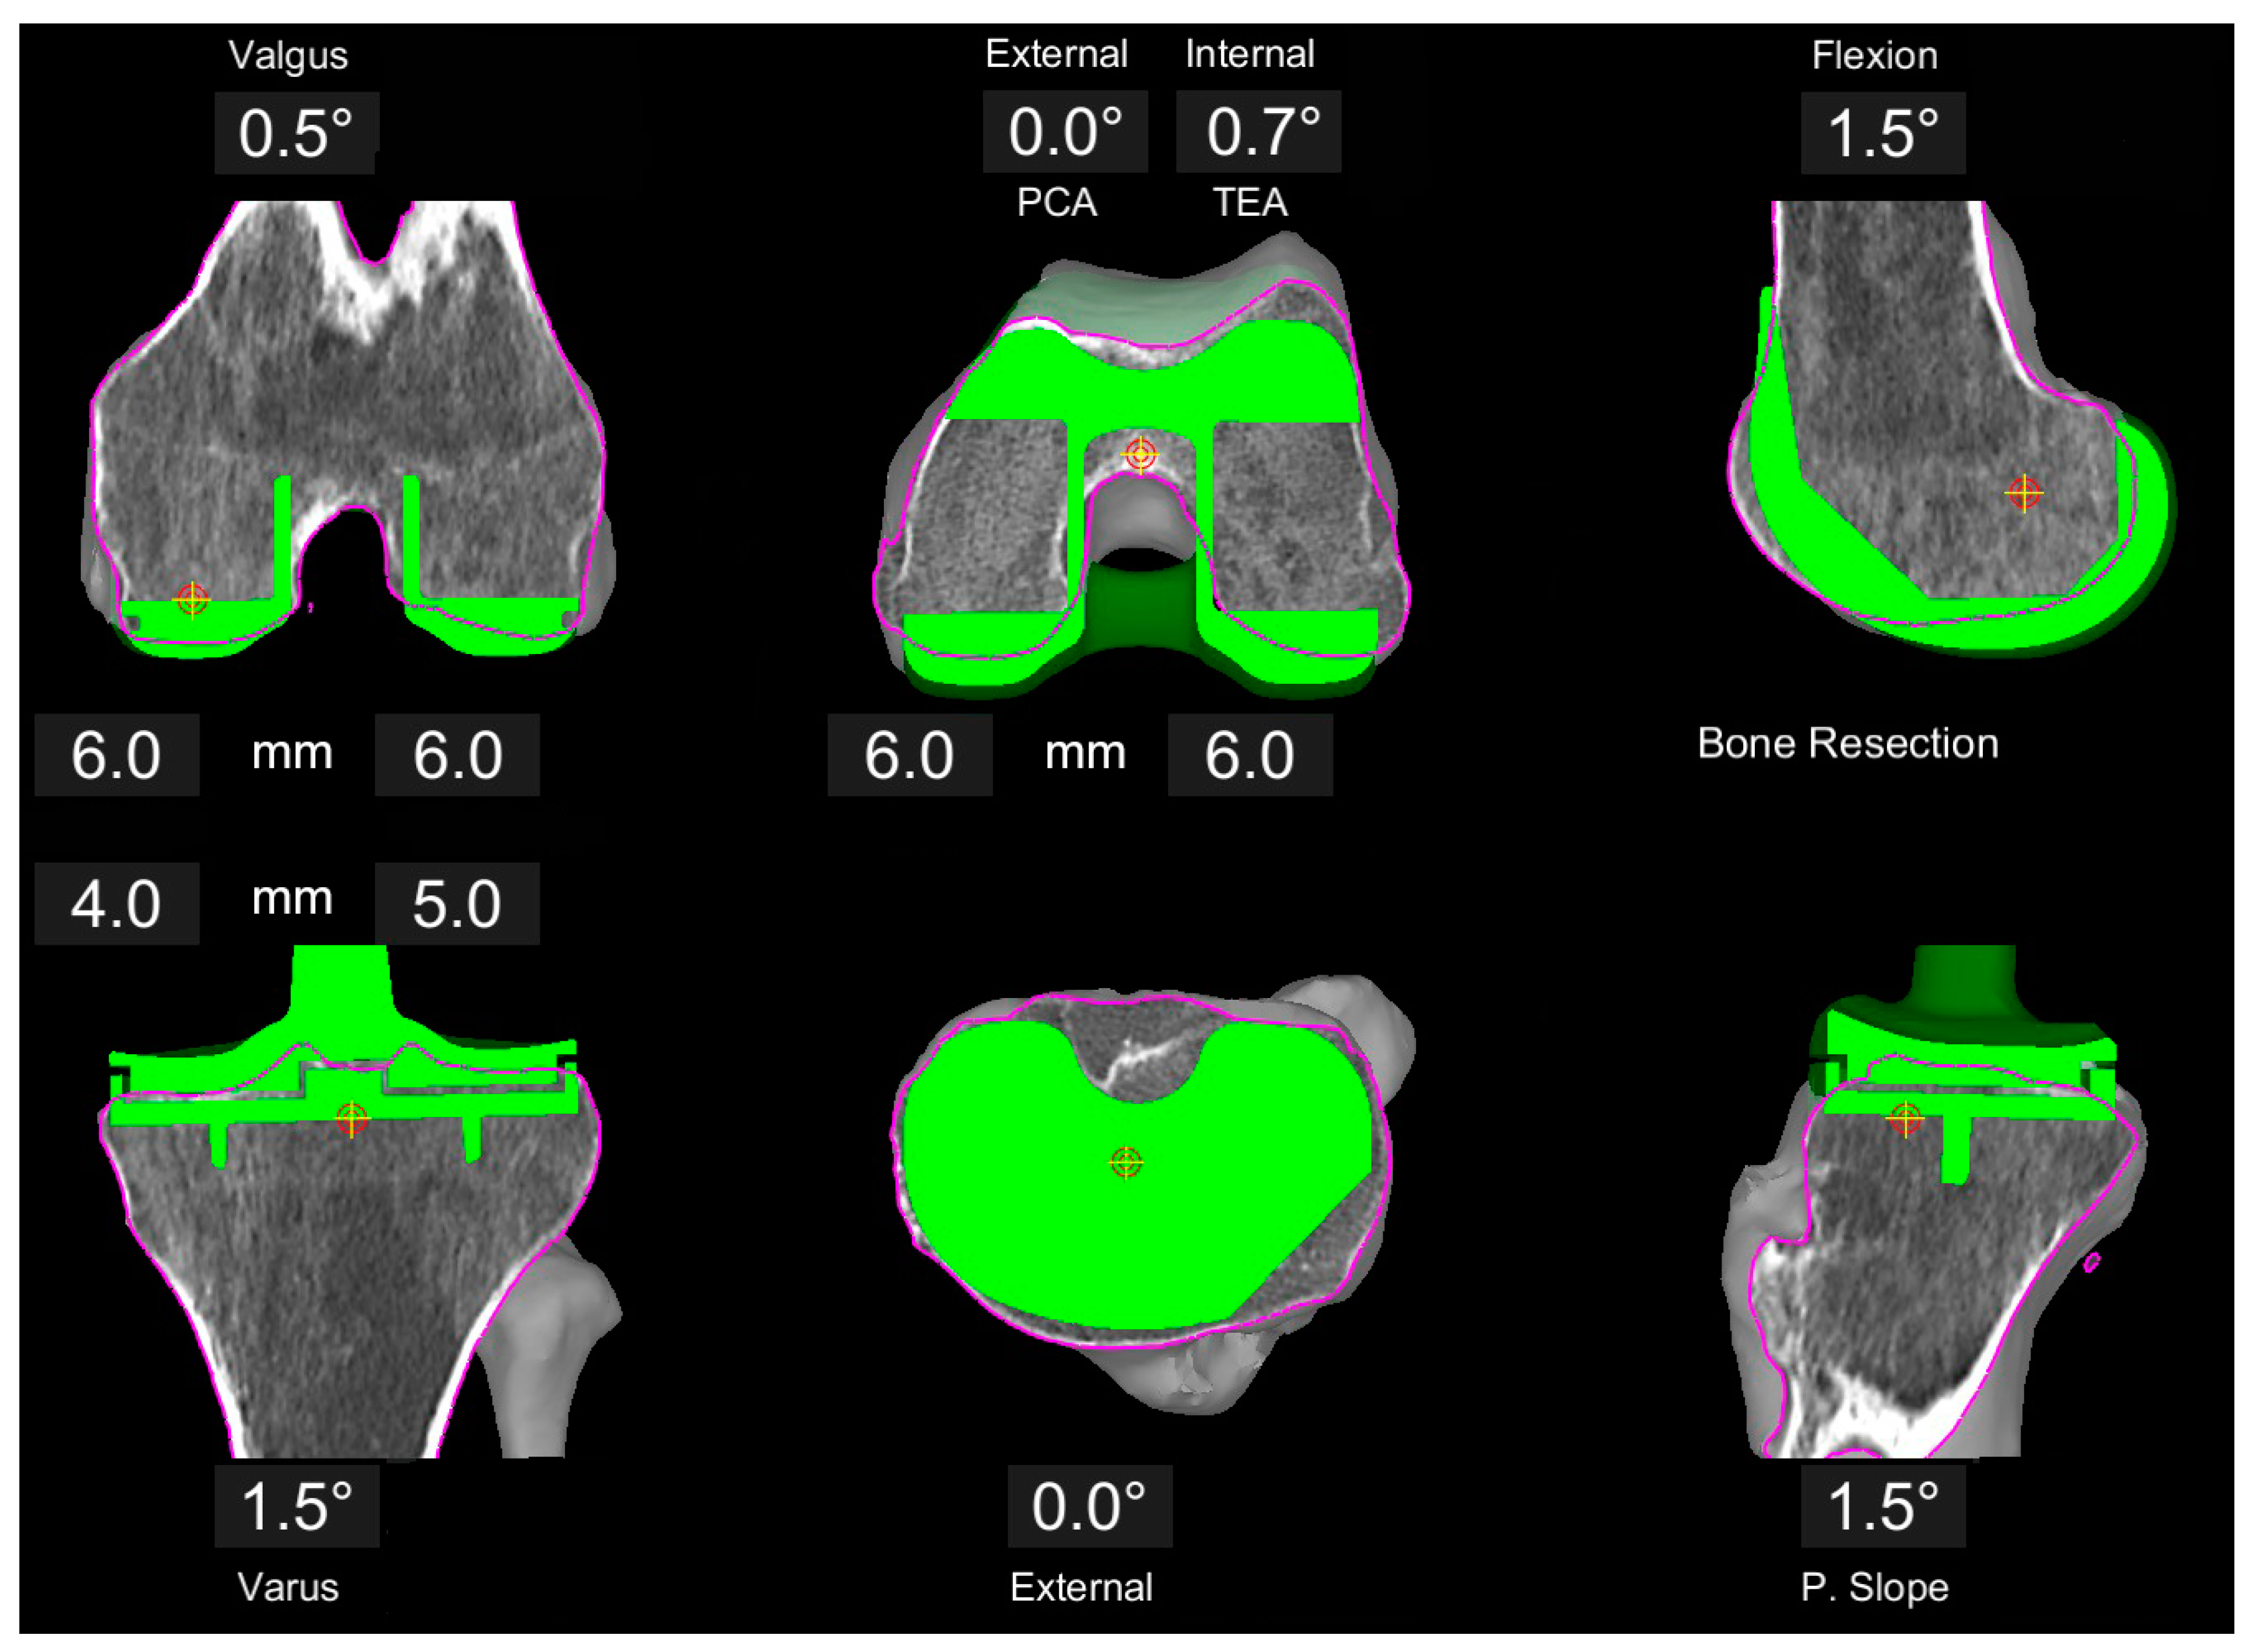

All surgeries were conducted with the MAKO robotic arm and the Triathlon PS knee system (Stryker, Kalamazoo, MI, USA). Prior to surgery, three-dimensional preplanning of the individualized component position using the proprietary MAKO software was conducted by the operating senior surgeon following the concept of kinematic alignment (KA) (Figure 1). First, the distal and posterior resections on the femur were set symmetrically at 6 mm bone resection. This results in an individual distal femoral angulation and a 0° rotation with reference to the posterior condylar axis (PCA) (individual rotation to transepicondylar axis (TEA)). In a second step, the femoral component size was defined to best reconstruct the anterio-posterior and medio-lateral dimensions without producing an overhang. Based on this position and size, the femoral flexion was adjusted to create a smooth anterior transition without notching.

Figure 1.

Example of image-based planning of the component position based on the principles of KA. Femoral resections are set to 6 mm each, resulting in 0.5° valgus position and 0.7° internal rotation with respect to the TEA. Tibia plan is preliminary at 1.5° varus, 1.5° slope and a resection level of 4 and 5 mm, respectively.

The tibia orientation was only preliminarily planned, starting with a rather conservative orientation for varus/valgus, slope, and resection level, and finally determined during surgery based on the soft tissue situation in order to achieve a symmetrically balanced extension space and an isometric gap in the medial compartment (see below).